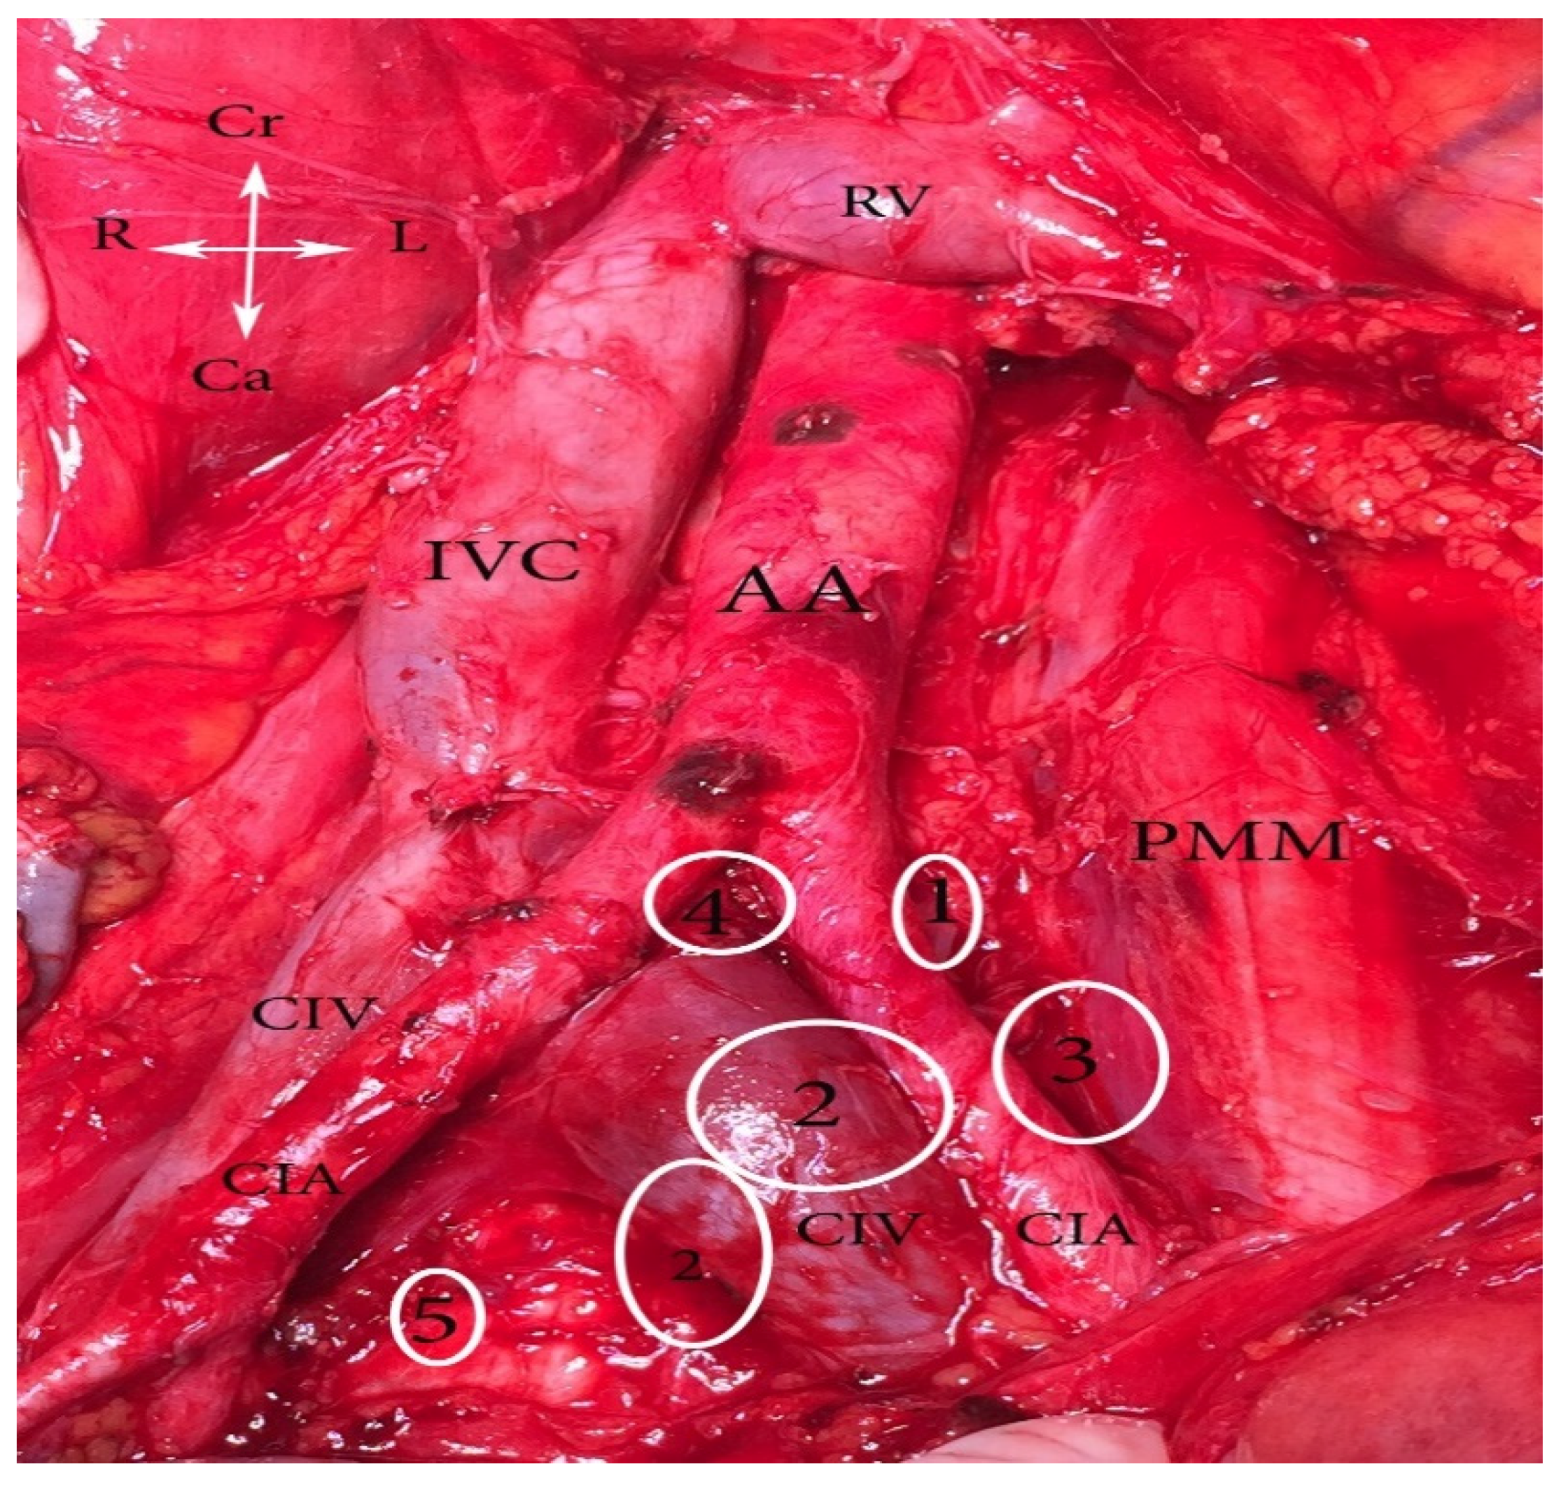

- Common iliac region dissection. Lymph nodes are removed ventrally and laterally from both common iliac vessels to the aortic bifurcation. Middle common iliac lymph nodes are located in the lumbosacral fossa. It is approached by medial retraction of the common iliac vessels and lateral retraction of the psoas muscle. The obturator nerve, entering the obturator fossa through the body of the psoas muscle, the iliolumbar artery/vein, and the lumbosacral plexus are exposed.

- Sacral (presacral) region dissection. After medial mobilization of the sigma-rectum, the peritoneum and the presacral fascia are incised medially to the right common iliac artery. Sacral lymph nodes, localized below the bifurcation of the abdominal aorta and inferior vena cava, in the triangle between the left and right common iliac vessels, are dissected [1,5,7,16,17,18,19].